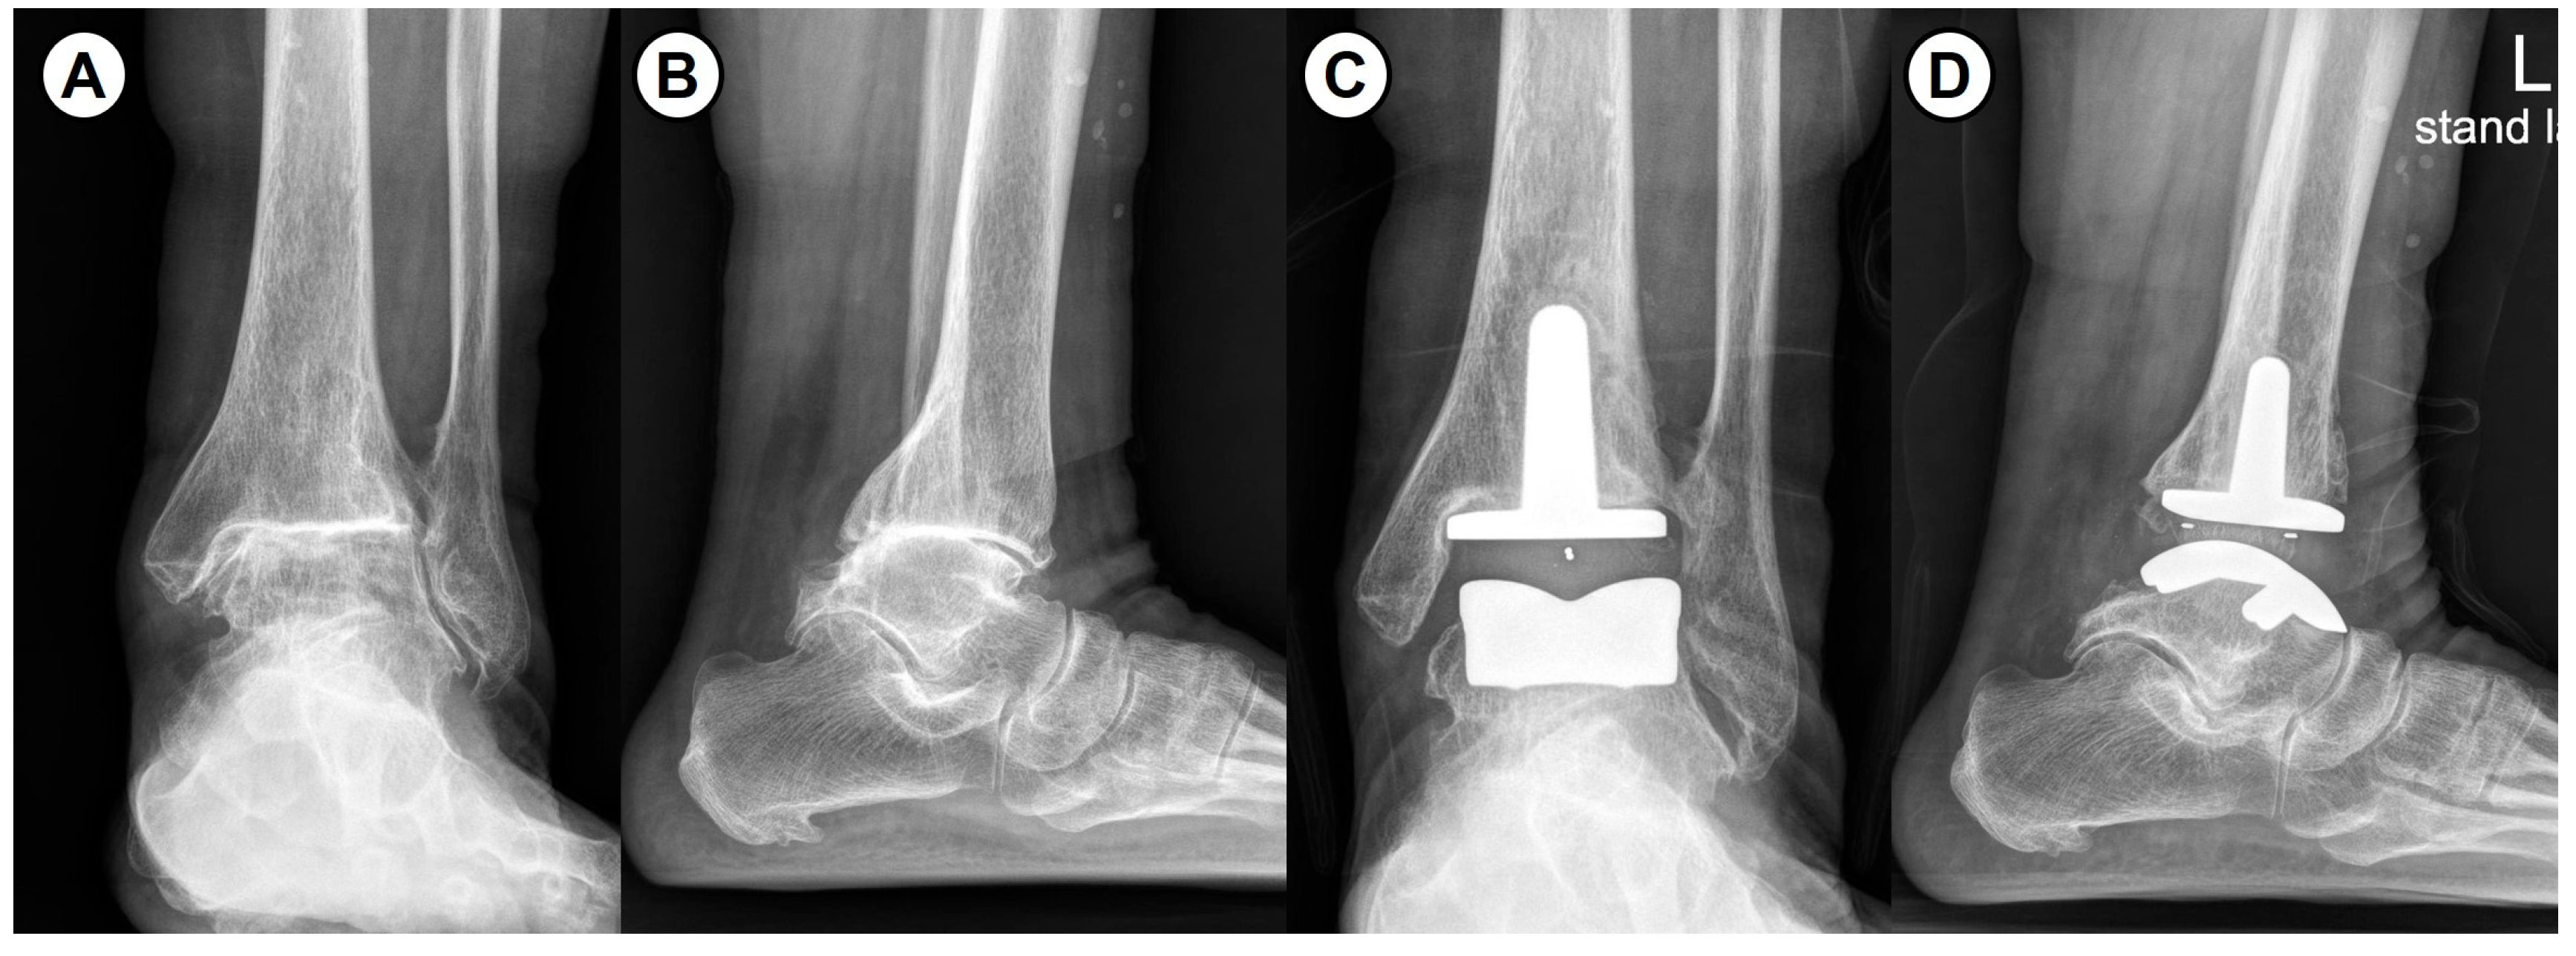

2.4. Clinical and Radiological Evaluation Methods

- Jeong, B.O.; Jung, H. Severe ankle osteoarthritis: Treatment with total ankle arthroplasty. J. Korean Foot Ankle Soc. 2018, 22, 8–15. [Google Scholar] [CrossRef][Green Version]